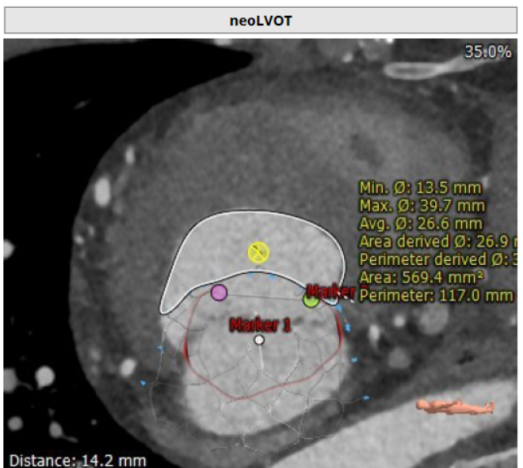

术前CT:收缩期NeoLVOT